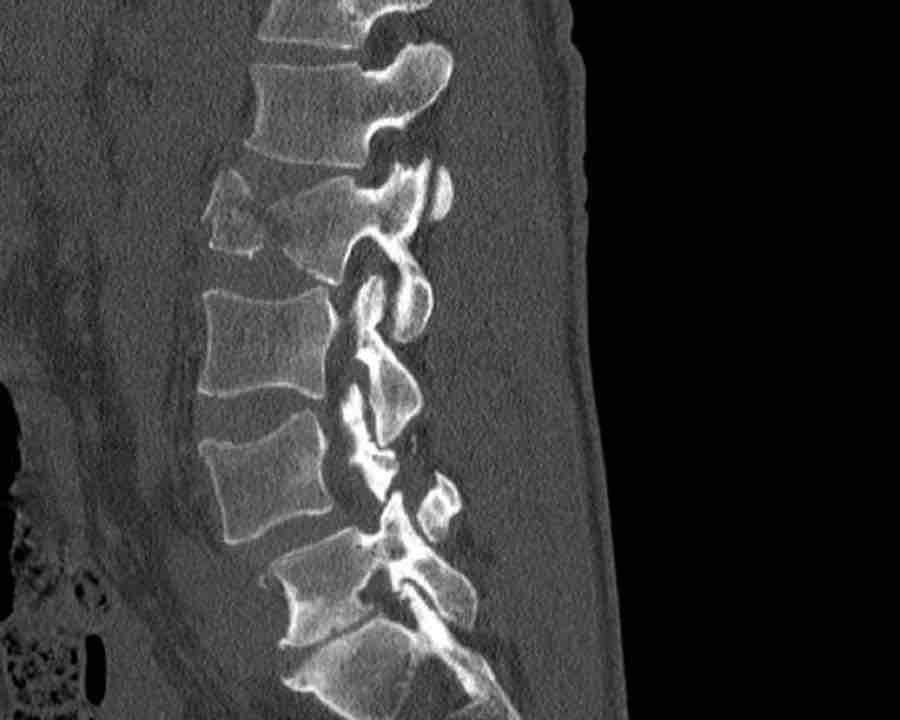

Findings

- The most severe level is L4/5 with dislocation (dotted lines)

- Facet fractures at L4 (arrows).

- A4 burst fracture (circle).

Conclusion:

Injury type C + A4 at L4/5.